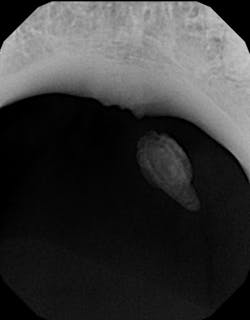

Diagnosis was confirmed with a radiograph of the affected area, showing a calcified stone that approximated the size and location of the lesion (figure 3). Once advised of the treatment options, the patient opted for surgical removal with a local specialist.